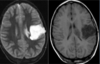

Q

A

Esclerose mesial temporal

Observe a perda de volume, que indica atrofia e causa aumento secundário do corno temporal do ventrículo lateral.

O sinal alto no hipocampo reflete a gliose.

How well did you know this?

Qual o padrão da Esclerose mesial temporal?

Atrofia hipocampal e hipersinal T2. Cerca de 10% dos casos são bilaterais (dificulta o diagnóstico). A etiologia é desconhecida, mas há uma relação entre STM e convulsões febris prolongadas no início da vida A esclerose mesial temporal pode ocorrer em associação com outras patologias, principalmente displasia cortical focal (dual pathology).